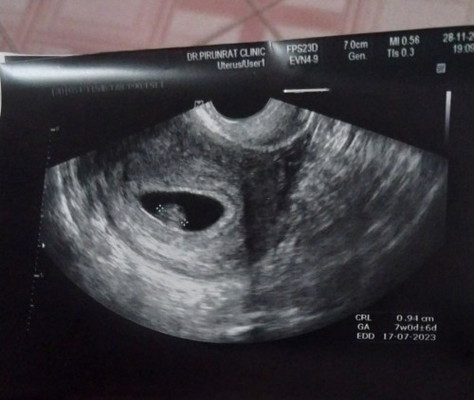

สรุปเจอจิ๋วน้อยแล้วนะคะหลังจากกังวลต่างๆนาๆตอนนี้ดีใจมากค่ะ

เจอน้องตอน7w6d. สุดท้ายก็เจอจนได้